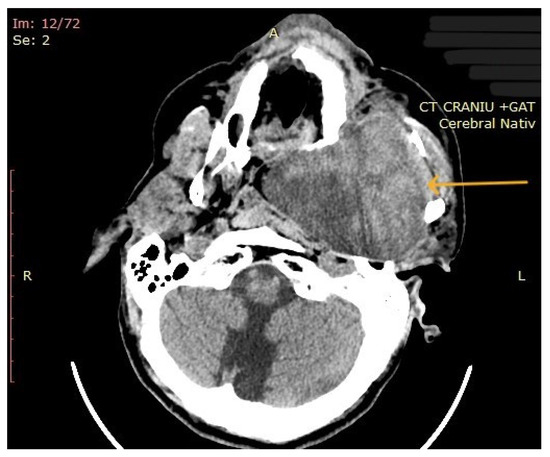

3.2. Imaging Aspects

| 10 | Left parapharyngeal region with maxillary and intracranial extension | Discomfort in breathing, chewing, swallowing, phonation, sleeping, regional pain, fatigue | 5 years | 10 cm | Benign tumor of soft tissue |